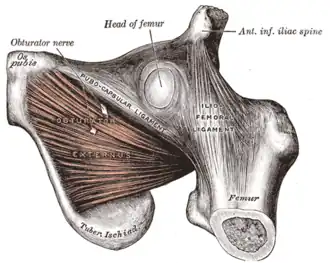

Capsule of hip-joint (distended). Posterior aspect. (Ischial tuberosity visible at bottom left.) | |